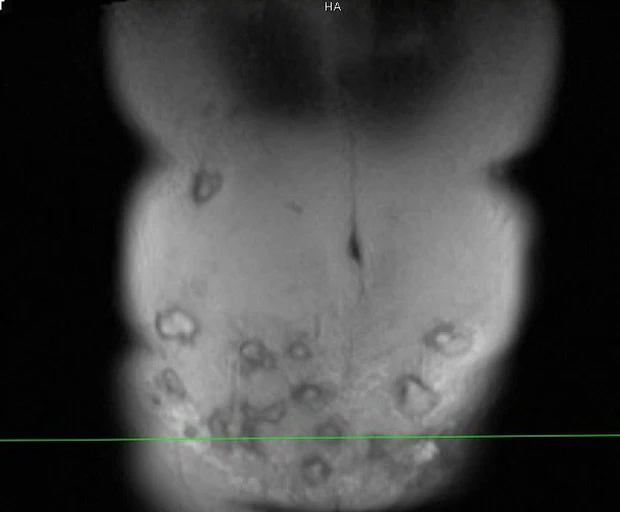

Các ổ áp xe trong thành bụng bệnh nhân sau tiêm tan mỡ. Ảnh: BSCC.

Bác sĩ Minh cho biết qua thăm khám, vùng thành bụng bệnh nhân bị viêm phản ứng nặng, vùng da ngoài thành bụng đỏ, nổi gồ ghề, sờ bên dưới có hàng chục khối tổ chức vón cục, áp xe.....

“Bệnh nhân này có thể tạo hình lại thành bụng, đồng thời xử lý được các khối áp xe (khoảng 20 khối lớn nhỏ). Tuy nhiên do vùng tiêm rộng nên việc lấy hết ổ áp xe không dễ dàng. Với những khối áp xe ở vị trí cao như hạ sườn, quá trình xử lý sẽ để lại sẹo, gây mất thẩm mỹ”, bác sĩ Minh chia sẻ.